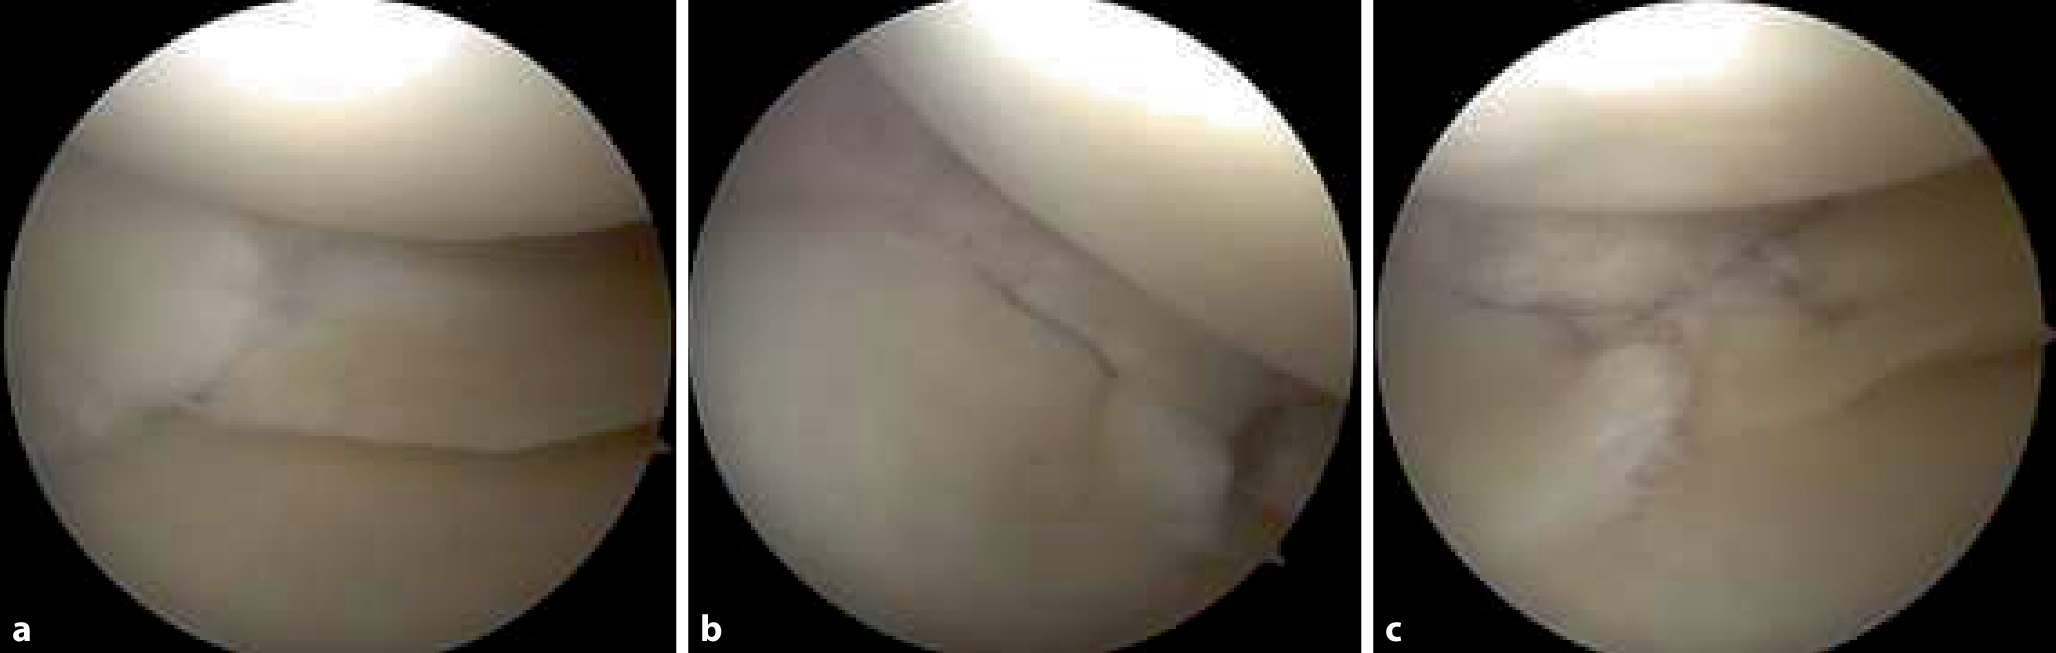

Neben einer Behandlung der radiären Verletzung des medialen Meniskus mittels Rebar-Nahttechnik (Abb. 3), wurde zusätzlich eine medial öffnende HTO zur Korrektur der varischen Beinachse und zur Entlastung des medialen Kompartiments geplant (Abb. 2b). Nach der operativen Versorgung, erfolgte die Röntgenkontrolle im anteroposterioren (Abb. 4a) und seitlichen Strahlengang (Abb. 4b). Zusätzlich wurden Beinganzaufnahmen zur Kontrolle der Winkelverhältnisse angefertigt (Abb. 4c). Da die Ergebnisse mit der Planung übereinstimmten, wurde dem Patienten eine komplette Entlastung für sechs Wochen, mit anschließender schrittweiser Erhöhung der Belastung bis hin zur Vollbelastung in den Wochen sechs bis acht, empfohlen. Während der ersten zwei Wochen soll das Bein mittels Knieorthese in Streckstellung und danach für vier Wochen auf 0/0/90° limitiert werden. Zwölf Wochen nach der Operation wurde eine Folgeuntersuchung durchgeführt, die ein nahezu beschwerdefreies Patientenbild zeigte.

Abb. 3

Arthroskopische Darstellung des medialen Meniskus vor der Durchführung der Rebar-Naht (a), nach der Platzierung des Rip-Stops (b) und nach Abschluss der Rebar-Naht (c)

In Bezug auf die Nahttechnik konnte zwischen parallel und überkreuzt gesetzten Nähten des Meniskus kein Unterschied hinsichtlich der „load to failure“ (LTF) festgestellt werden [5]. Dagegen konnte die Rebar-Methode im unmittelbaren Vergleich einer höheren Belastung als die anderen beiden Nahttechniken standhalten [5]. Wie oben beschrieben, kommt es bei dieser Kombination aus vertikalen und horizontalen Matratzennähten, zusätzlich zu einer Verstärkung der zirkumferenziellen Fasern und zur Rekonstruktion der Ringspannung [5]. Aufgrund dieser empirischen Argumentationskette entschied man sich auch im vorliegenden Fall für eine Rebar-Naht des medialen Meniskus.